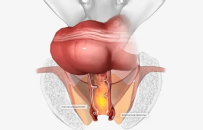

Abdomino Perineal Pesection Surgery

Anterior Resection of Rectum

Hemicolectomy-left

Hemicolectomy-right